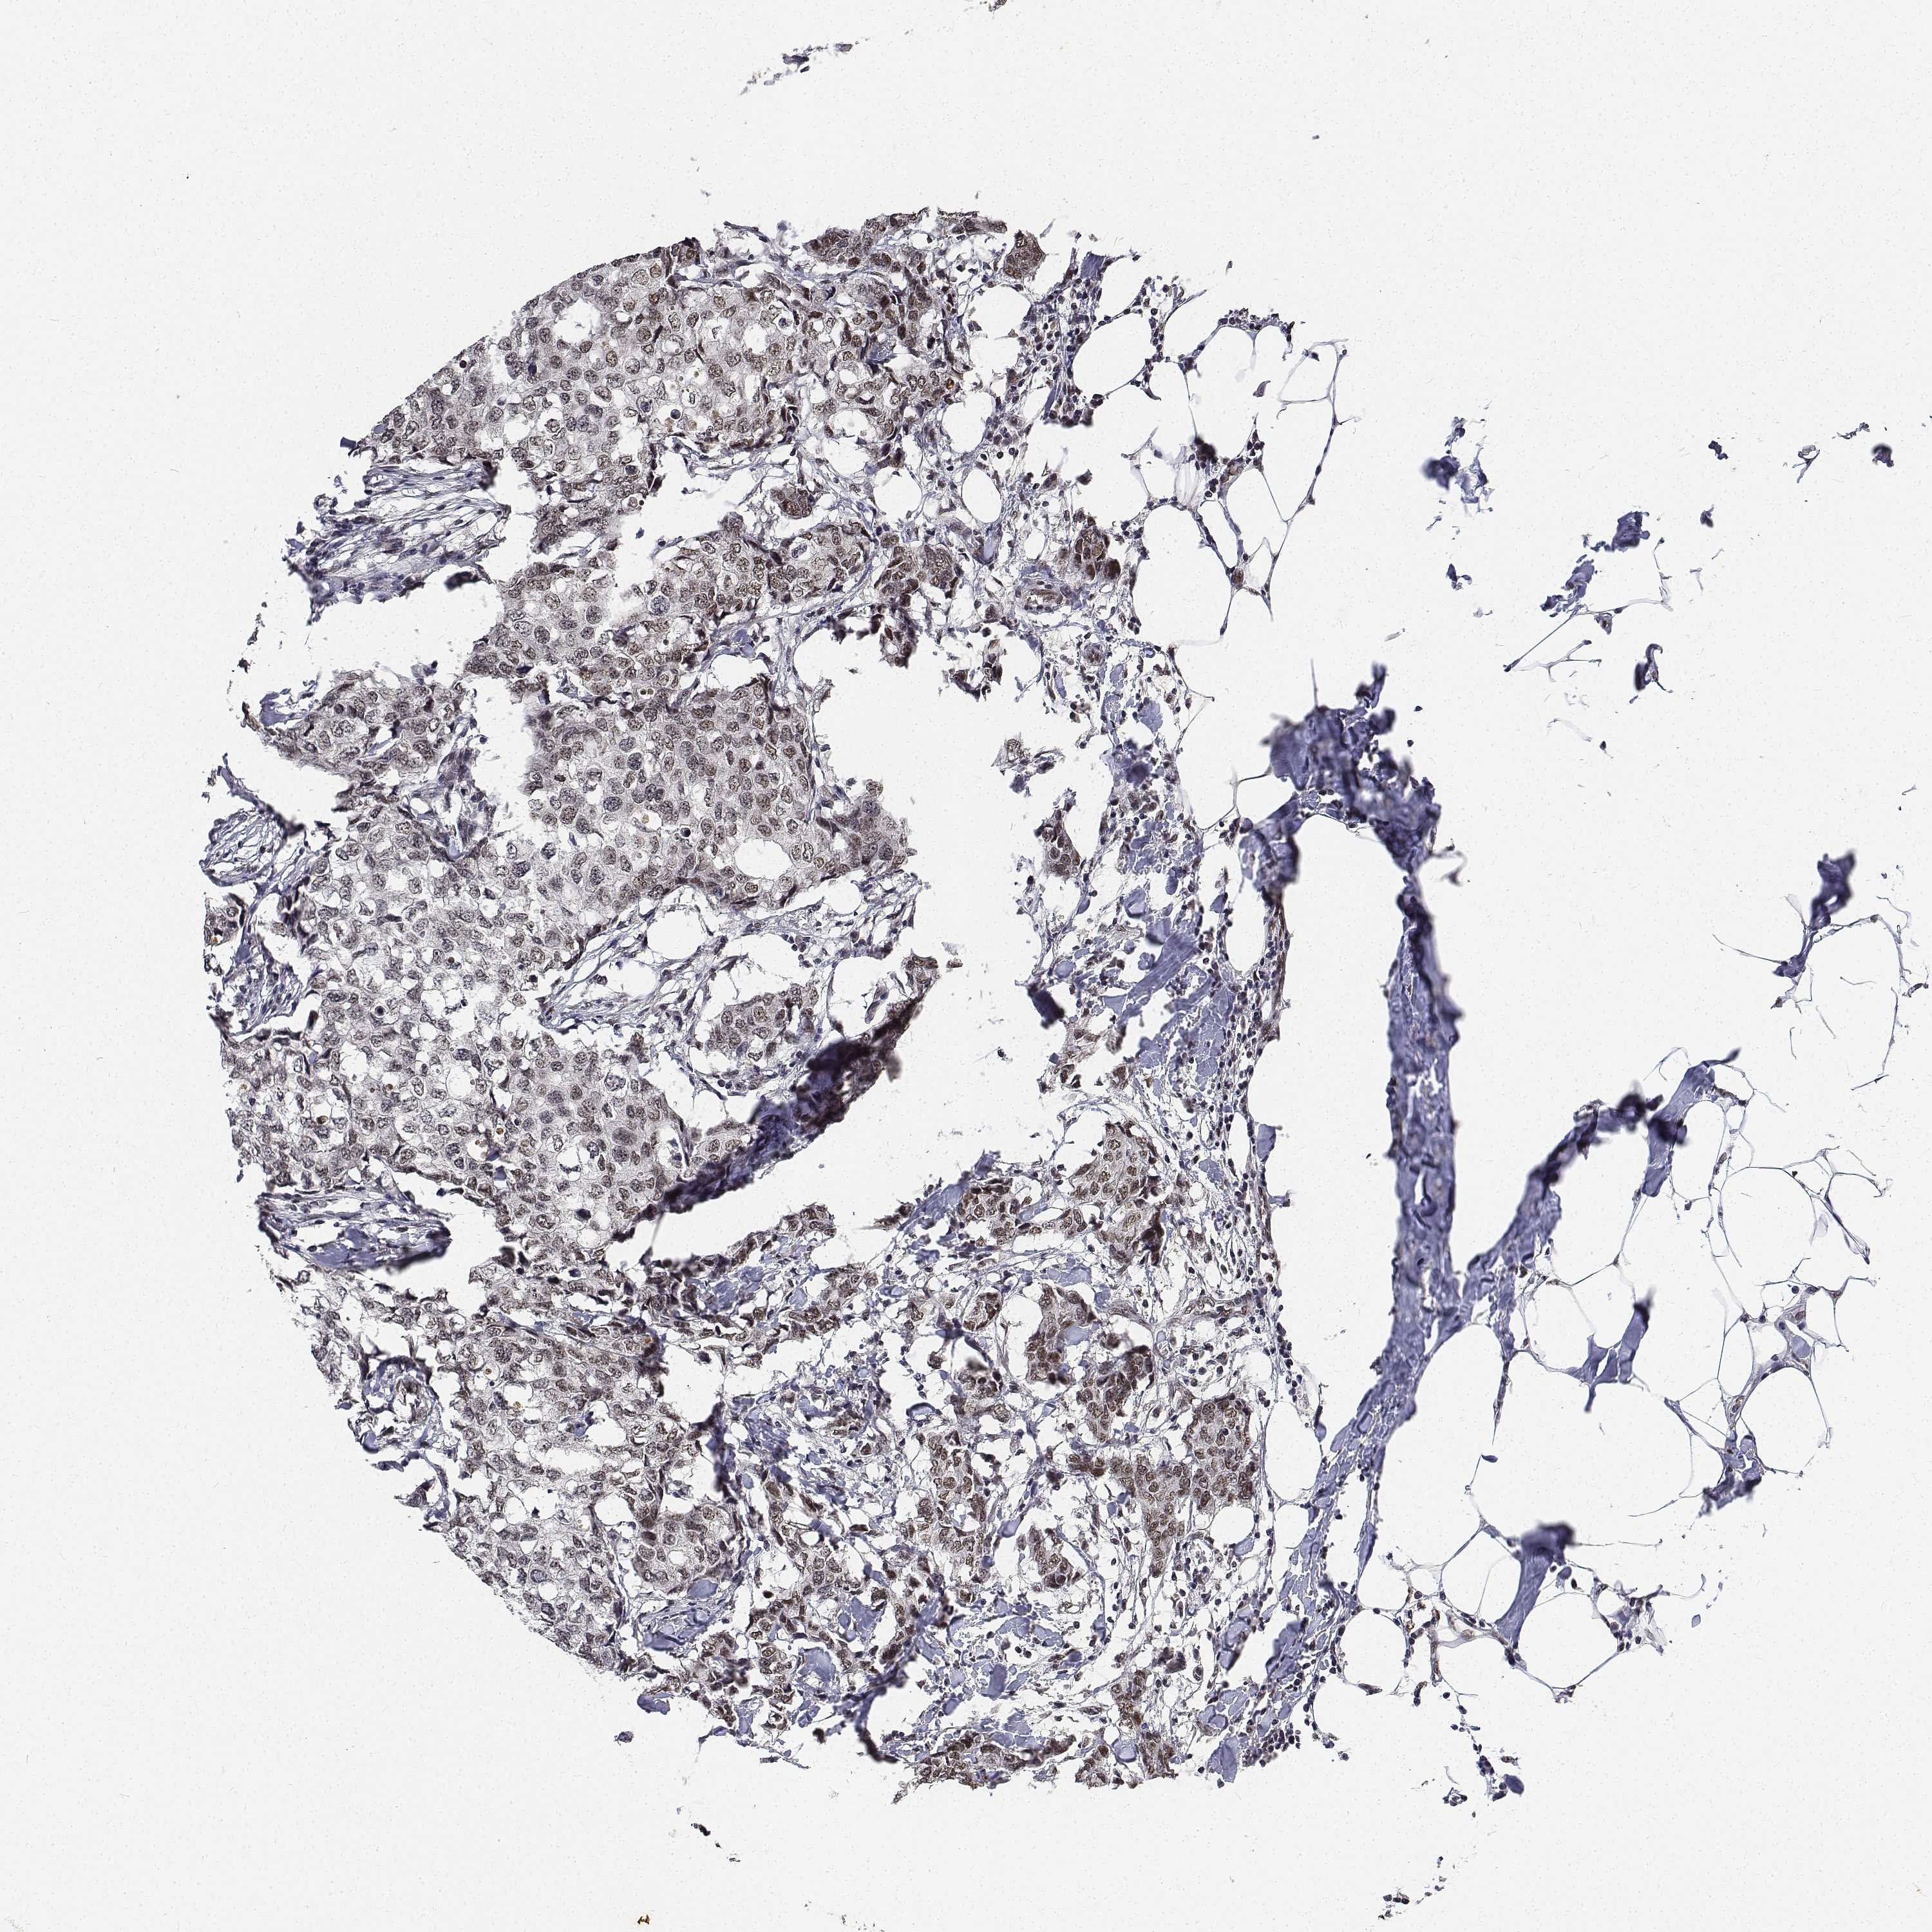

CANCER BREAST CANCER Show tissue menu

BRCA TCGA BRCA VALIDATION PROTEIN EXPRESSION